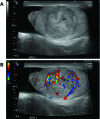

Testicular capillary hemangioma is a rare benign vascular tumour. We report a case of a 66-year-old man who underwent an uncomplicated radical orchiectomy for a painless left testicular mass. Pathology showed capillary hemangioma of the testis. There are only 22 cases reported in the English literature, including the presented case. Appropriate intra-operative recognition of this entity is vital to assess for potential testicular-sparing surgery.